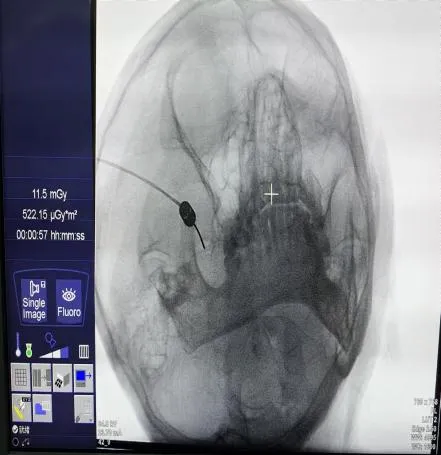

近日一名八十多岁的患者刘奶奶(化名)近3年来饱受左侧额面部发作性疼痛折磨,近期疼痛更是加重,于是前往荣昌区人民医院疼痛科就诊。入院时刘奶奶面容痛苦、精神萎靡,经疼痛评分后为“重度疼痛”,且由于进食、刷牙等诱发疼痛导致无法正常进食与刷牙,刘奶奶还出现全身乏力与多发口腔溃疡等症状。经过术前准备,在DSA引导下行左侧三叉神经半月节微球囊压迫术,术中,医务人员采用专用穿刺针精准穿刺,使用微球囊对三叉神经半月节进行压迫,从而消除了患者的疼痛,整个过程用时不到30分钟,术后,刘奶奶疼痛消失,第2天恢复正常饮食,她的脸上露出了久违的笑容。

近一年来,荣医疼痛科在C型臂或DSA影像引导下运用穿刺针为多名患者实施的三叉神经半月节射频热凝术或三叉神经半月节微球囊压迫术,经术后长期随访,患者疼痛完全消失。